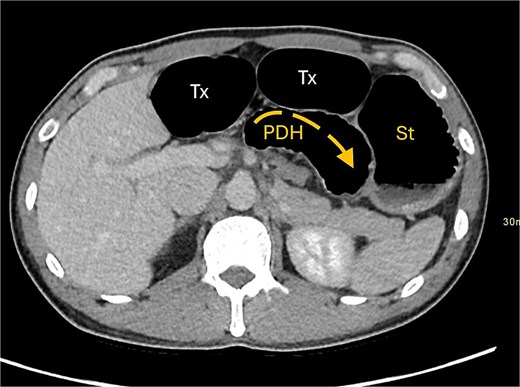

A contrast-enhanced computed tomography (CT) scan of the abdomen and pelvis demonstrated a large bowel obstruction with a transition point at the distal transverse colon with swirling of the mesentery. Downstream large bowel was collapsed. Upstream dilatation included the terminal ileum suggested an incompetent ileo-caecal valve. The gastric antrum was also involved in the internal hernia, resulting in gastric outlet obstruction. See Figs 1–5.

Axial CT image displaying transverse colon in paraduodenal hernia (PDH) with resulting distension of transverse colon (Tx) and stomach (st).